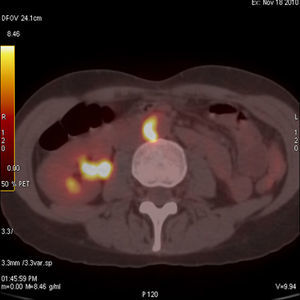

Case 1We present the case of a 43-year-old woman with a history of chronic sinusitis, corneal ulcers and relapsing blepharitis, treated with 30mg of prednisone day after being studied in the infectious diseases unit due to persistent low-grade fever of 37.5°C, where a microbiological origin was ruled out. A few weeks after presenting clinical improvement, her fever returned for 15 days, improving with antipyretics; her blood pressure (BP) levels were 100/60mmHg and she presented paresthesias of her left foot. An electrophysiology study was conducted and showed an electroneurographic pattern of conduction block at the left distal posterior tibial nerve, compatible with peripheral nervous system vasculitis. Laboratory tests showed mild leukocytosis with a small leftward shift, erythrocyte sedimentation rate (ESR) of 97mm (normal values up to 25mm) and C reactive protein (CRP) of 1.22mg/dl (normal to 0.5mg/dl) with negative antineutrophil cytoplasm antibodies (ANCAS). A cerebrospinal fluid study showed pleocytes and lymphocytes. The first clinical suspicion was polyarteritis nodosa (PAN), so we decided to perform a muscle and sural nerve biopsies that were nonspecific. Because of the history of sinusitis, the diagnosis of microscopic polyangiitis or Wegener's granulomatosis (WG) had to be ruled out, which we did after a biopsy of the affected mucosa. At all times peripheral pulses remained present and symmetrical, with no significant differences in BP between the 2 arms; there were no murmurs on auscultation of the aorta or subclavian arteries and the patient did not complain of fatigue or discomfort and presented no claudication. Within 10 days of admission she presented occipital and frontal headache with photophobia and little improvement with analgesic treatment as well as hypertension (160/95mmHg) which responded with the administration of ACE inhibitors. Keeping with our clinical suspicion of vasculitis we conducted a magnetic resonance angiography (MRA) of the aorta (Ao), which showed no abnormalities, a brain MRI which confirmed the existence of pachymeningitis and a thoracoabdominal CT that showed a small infrarenal aneurysm cm2 diameter. Finally, we performed a PET-CT which showed hypermetabolic lesions of the pulmonary bifurcation and the abdominal Ao wall (Fig. 1), which along with gender, age, involvement of large vessels (Ao and pulmonary), the presence of aneurysms, the negativity of ANCAS, the result of the biopsy and exclusion of PAN and GW, very likely led the diagnosis of Takayasu's arteritis (TA) with the added difficulty of performing a biopsy of the affected area.